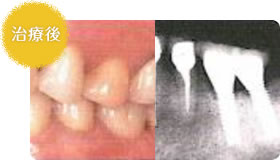

- 上顎は多くの歯がありません

- 総入れ歯で歯を入れて噛めるようになりました

歯が全部抜けてしまって、支える歯がなくなると、総入れ歯(総義歯)になります。総入れ歯は吸盤の原理でくっついているため、お口の中の動く筋肉や舌の動きなどとバランスをとりながら安定させることが総入れ歯には必要です。

歯をほとんど失ってしまった場合